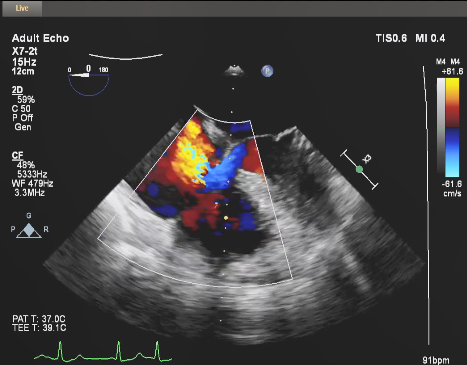

经导管三尖瓣修复系统(Trialign)修复术后,超声(图3),三尖瓣瓣环内径约3.95cm,三尖瓣等量反流(2级)。

图3:术后超声